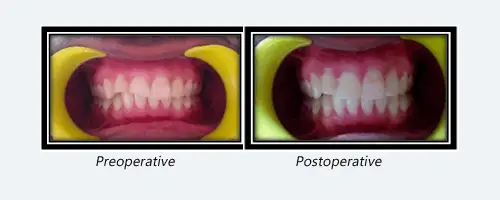

Fragment Reattachment After Traumatic Injury

A 22 year old Patient reported with a history of trauma causing fracture of upper anterior teeth few hours back , after thorough examination , a diagnosis of Ellis class III fracture in relation to 11 and 12 was made .Fractured segments were attached palatally at subgingival level . Intensive treatment plan was charted, and after acquiring patient’s consent, reattachment of the fractured segment after root canal treatment was planned on the same day . Fractured segments were extracted atraumatically and placed in normal saline and Single sitting RCT with fibre post was done to relieve the pain. After that gingivectomy was performed in relation to same teeth and fractured segments were reattached to their corresponding position with resin cement . Follow up was done after a month and patient was symptom free and happy.

Composite Veenering

The patient reported to the department of Conservative Dentistry & Endodontics with the chief complaint of fractured upper front teeth. The patient was diagnosed with Ellis Class I wrt 11 & Class II fracture wrt 12. The treatment Plan was formulated as direct composite build up. The patient was satisfied with the post operative appearance.